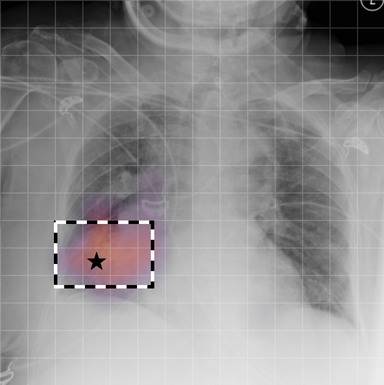

In Figure A.3, we show examples of self-attention rollout [1] maps for pleural effusion and consolidation, including radiologist-annotated bounding boxes surrounding the corresponding pathology in each prior and current image.

To model the attention flow through the transformer encoder block, we first average each attention weight matrix across all heads, subsequently we multiply the matrices between every two layers. For every block we add the identity matrix in order to model the residual connections. Last, we only keep the top 10 of attention weights per block to reduce noise in the final rollout map. In contrast to [21], we do not visualize the rollout map with respect to a [CLS] token. Instead, we choose a reference image patch from the center of the radiologist-annotated bounding boxes, marked with in Figure A.3.

We find that the rollout maps in Figure A.3 are in good agreement with radiologist-annotated bounding boxes, i.e., the reference patch attends to other patches within the bounding boxes in the prior and current image. In addition, we find that BioViL-T is robust to pose variations, e.g., in Figure A.3 (a) we show that despite the vertical shift between prior and current image, the reference patch attends to the correct image patches in the prior image.

To further assess the robustness of BioViL-T against pose variations between prior and current images, we performed multiple rotations to the prior image within a pair and computed rollout maps from the same reference patch in the current image. Figure A.5 shows that BioViL-T consistently attends to the corresponding anatomical region independently of the spatial transformation applied, demonstrating that registration is not needed.